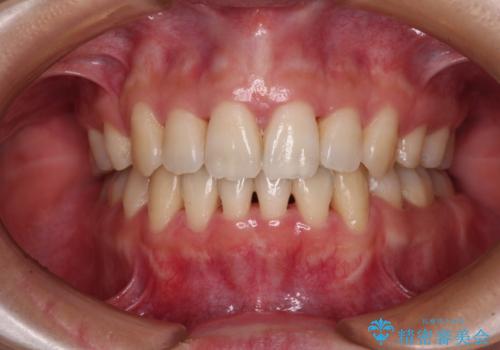

【ハーフリンガル】重度の叢生

担当医 河口智英